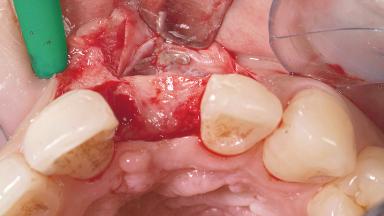

Late Placement of an Implant in a Maxillary Left Central Incisor Site

A 30-year-old female patient had lost tooth 21 and was referred to our clinic for consultation and treatment. Due to advanced apical infection, tooth 21 had been extracted two months earlier at another clinic and an acrylic-resin tooth had been bonded to the adjacent teeth. The patient desired implant treatment to avoid any damage to the adjacent natural teeth. While the patient had no history of any systemic disorder, she was a heavy smoker and exhibited medium to advanced periodontitis in the entire jaw. After the initial treatment to achieve a pocket probing depth of less than 4 mm and no bleeding on probing, a decrease in the height of the papillae mesial and distal to the extraction site and overall gingival recession were observed.

Bone Augmentation Horizontal|Staged

Augmentation Materials Autogenous chips|Membrane

Bone Volume Horizontally and vertically sufficient Horizontally deficient Deficient vertically or deficient vertically AND horizontally

Bone Volume Deficient horizontally, requiring prior grafting